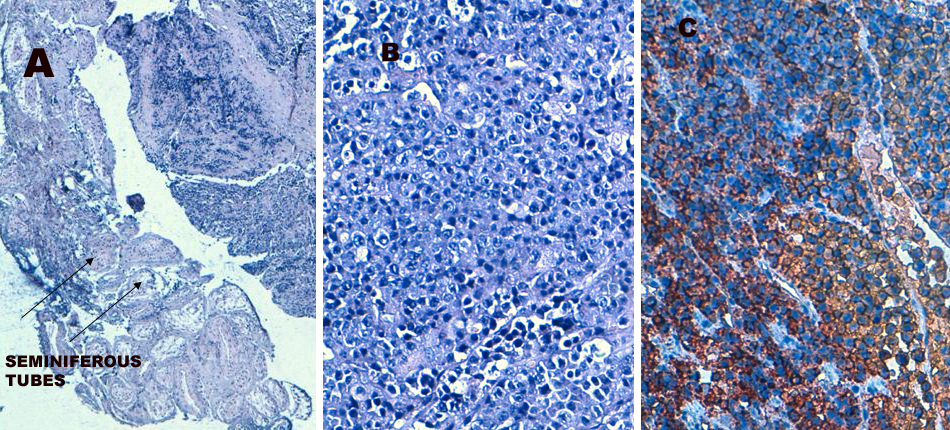

Figure 1. Plasma cell  proliferation involving testicular parenchyma (A). Plasmocytoid cells (B). Tumor cells intensively marked by the anti-CD138 antibody on immunohistochemistry (C).